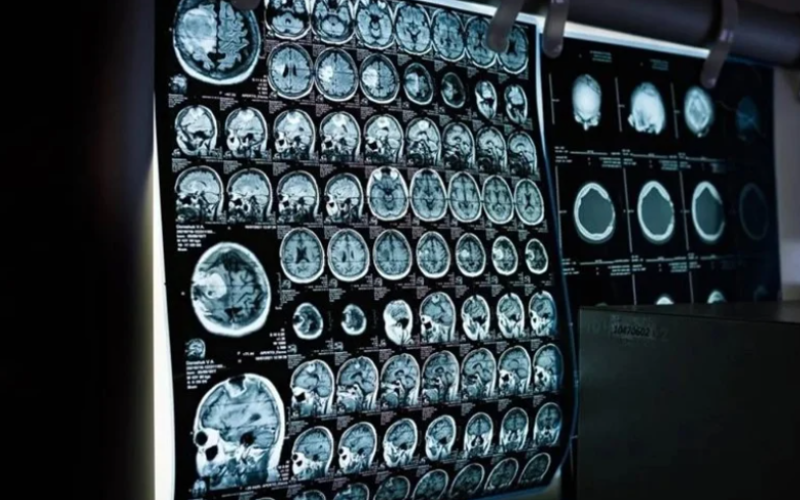

اختبار منزلي بـ3 دقائق يكشف علامات الزهايمر قبل سنوات من التشخيص

أظهرت تجربة أن اختباراً لموجات الدماغ لا يستغرق سوى ثلاث دقائق، قد يكشف عن مؤشرات لمشكلات في الذاكرة مرتبطة بمرض الزهايمر قبل سنوات من إمكانية التشخيص السريري.

ويرى الباحثون أن هذا الاختبار قد يشكل أداة زهيدة التكلفة لمن يواجهون صعوبة في الحصول على تشخيص، ويمكن استخدامه في أماكن متعددة، بما في ذلك المنازل، بحسب وكالة الأنباء البريطانية (بي إيه ميديا).

وجرى تطوير الاختبار الجديد، الذي أطلق عليه اسم "كرة السرعة"، في جامعة باث، ويعتمد على تقنية قياس النشاط الكهربائي للدماغ من خلال وضع حساسات صغيرة على فروة الرأس، ويعرض على المرضى صوراً متسارعة ثم يسجل الاستجابة التلقائية للدماغ.

وشملت الدراسة، التي قادها خبراء من جامعتي باث وبريستول ونشرت في مجلة "اتصالات الدماغ"، 52 مريضاً يعانون من ضعف إدراكي طفيف، أي تراجع في الذاكرة أو مهارات التفكير، و54 شخصاً من كبار السن الأصحاء.

وتقدر جمعية الزهايمر أن هناك نحو 982 ألف شخص مصاب بالخرف في المملكة المتحدة، لكن أكثر من ثلثهم لا يحصلون على تشخيص، ومن المتوقع أن يرتفع العدد إلى 1.4 مليون بحلول عام 2040.